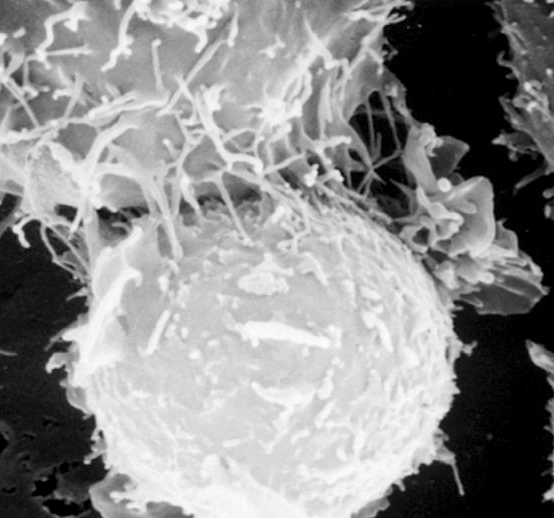

Т-киллер, атакует раковую клетку

Почему так происходит? Раковые клетки появляются в нашем организме постоянно, но иммунные тельца распознают и убивают их, защищая организм от развития опухоли (на картинке, Т-киллер, атакует раковую клетку). Но нервная система, подавленная тяжелым психическим переживанием, организовать сопротивление иммунитета не может и раковые клетки легко его обманывают.